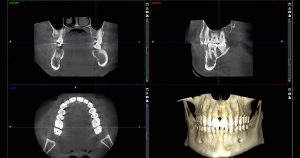

4. Cone beam computed tomography – It acquires data volumetrically providing three–dimensional radiographic images for the assessment of the dental and maxillofacial complex, facilitating dental diagnosis. Used to detect potential extra canals before endodontic treatment, pre-surgical planning for an implant, third molar positionings, benign calcifications, cysts, and tumors in the jaw.